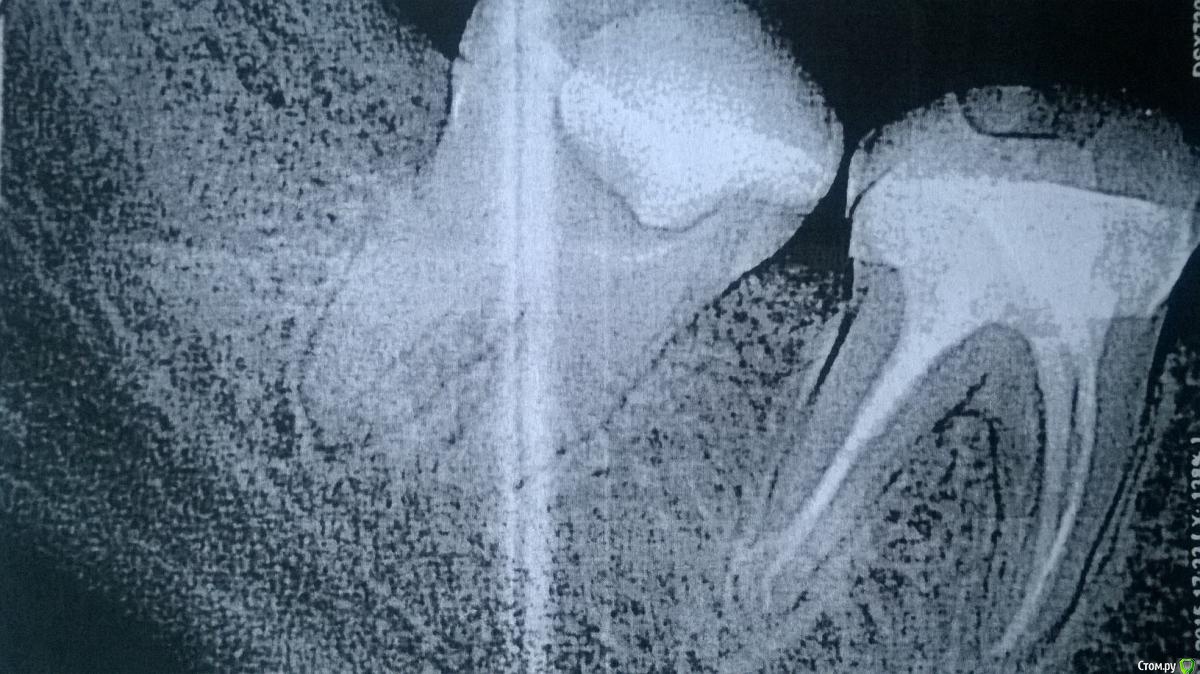

Lana54rus Опубликовано 23 мая, 2015 Поделиться Опубликовано 23 мая, 2015 (изменено) Доброго времени суток! очень нужен совет. Ситуация запутанная, но пытаюсь в ней хоть как-то разобраться.1) Итак: проходила стоматологическое лечение. Во время лечения начал ныть зуб 4.7. - ныл месяц (недепульпированный, живой), болел периодически. Доктору сообщала, но на это никто не отреагировал, ЭОД, и холодовую пробу не проводили, сказали, что на томограмме с этим зубом всё нормально. Спустя две недели попала по острой боли к другому доктору и на ранее выполненной дентальной томограмме заявили о наличии острого периодонтита (воспаление на верхушке корня) и записали на неотложку к другому доктору. Доктор промыл каналы, но прошёл их лишь наполовину (лечили под микроскопом), о чём мне и сообщил, (сказал, что так надо, полностью пройдут потом). Положил каласепт и закрыл всё временной пломбой, сказал придти через полторы недели. Когда чистили каналы, было зверски больно, не помогла даже анестезия.2) Через два дня стало совсем плохо - обратилась на неотложку в другую клинику (припухла щека и сильно ломила челюсть в области больного зуба). Пытались пройти каналы - доктор сказал, что один из каналов перфорированный, пытался пройти канал с перфорацией, но не получилось (при каждом посещении ставил пасту "каласепт")..3) Обратилась в другую клинику, где также попытались пройти каналы, но потом сообщили, что там ложный канал и сказали о срочной необходимости данный зуб удалить.4) Я отказалась, пошла к другому доктору. Доктор сказал, что зубы с перфорациями лечат, а не удаляют - все каналы прошли, перфорацию закрыли. Запломбировали каналы сразу же на постоянной основе. Зуб болел ещё две недели после пломбировки каналов, успокоился только неделю назад. Вчера поставили постоянную пломбу. К своему последнему доктору, претензий нет никаких, доктор что мог, то сделал.Вопрос (для собственного успокоения и чтобы хоть как-то понять ситуацию):1. Каковы прогнозы для подобного зуба?2. Учитывая вышеизложенное, а также картину на снимках о чем здесь следует говорить: об остром или хроническом периодонтите (ранее была высказана гипотеза, о том, что у меня уже был периодонтит и нерв в зубе умер уже давным давно). На данный момент томографией из первой клиники не располагаю, а потому могу обрисовать ситуацию лишь на словах.Заранее, спасибо за ответы.а) снимок сделанный во время лечения во второй клинике;б) снимок во время прохождения каналы сделанный в третьей клинике, где зуб настоятельно рекомендовали удалить;в) окончательный вариант пломбировки каналов. Изменено 23 мая, 2015 пользователем Lana54rus Ссылка на комментарий

St. Опубликовано 23 мая, 2015 Поделиться Опубликовано 23 мая, 2015 Каковы прогнозы для подобного зуба? Прогноз сомнительный, т.е. какое-то время простоит, сколько конкретно - никто не знает. Четыре доктора на один зуб и перфо - это не очень хорошо.Через 6 мес. нужно будет сделать контрольный снимок. Пока наблюдайте. Если всё ок - скорее всего на него нужна будет коронка. Ссылка на комментарий